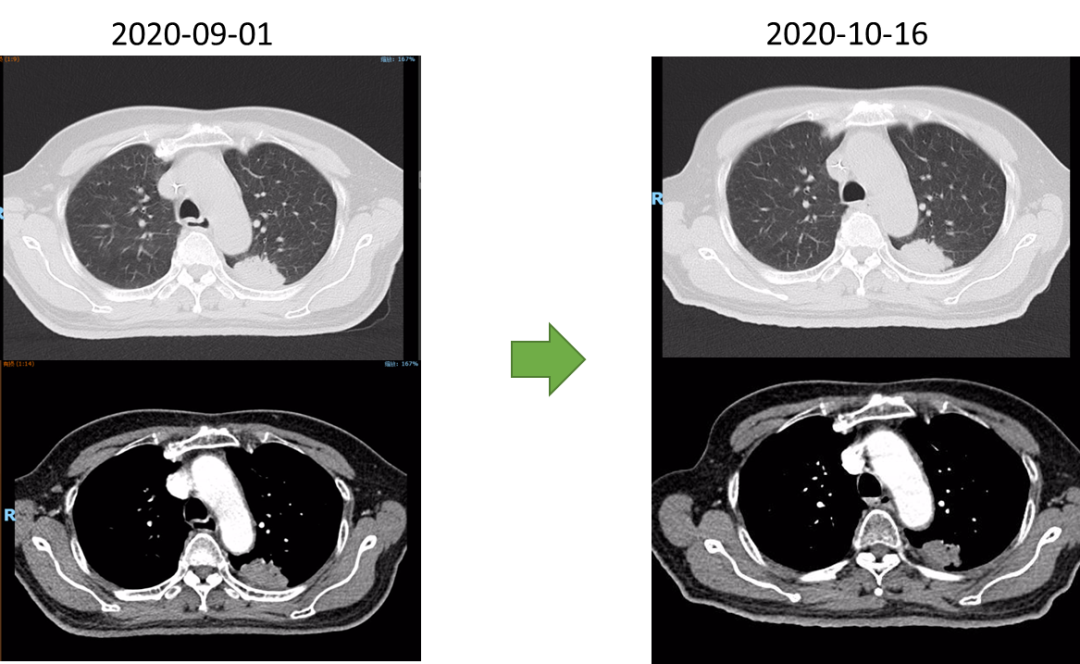

2020-08-27行放疗CT定位。2020-09-07~2022-10-23行肺部、食管放疗。

GTVp1为食管肿瘤,GTVp2为肺肿瘤。

分割方式:

95%PGTVp1:60Gy/2Gy/30F;

95%PGTVp2:60Gy/2Gy/30F;

后肺原发灶补量照射:95%PGTVp2:8Gy/2Gy/4F。

放疗同期行同步化疗+靶向治疗,具体方案为:洛铂50mg d1 q21d+尼妥珠单抗400mg Qw。放化疗前开始行重组人血管内皮抑制素(恩度)30mg d1-7q3w抗血管靶向治疗。放化疗结束后给予抗血管靶向及针对肺原发灶TKI靶向治疗维持,TKI靶向:克唑替尼250mg Bid po Qd。治疗后3个月,患者拒绝继续恩度靶向治疗。治疗后6月患者拒绝克唑替尼治疗。考虑肺癌为驱动基因阳性型,未能行食管癌治疗后免疫治疗维持。

疗效评估及随访

放射治疗结束复查胸部CT:左肺上叶尖后段与左肺下叶背段交界处病灶较前略显缩小,现最大横断面约2.6*2.8厘米,边缘可见毛刺,增强后可见强化,邻近胸膜稍增厚。食道中段管壁增厚,上下累及约4.5厘米(约胸5/6椎间隙水平至胸8椎体上缘水平),增强后强化程度似较前有所减低,隆突下见境界不清淋巴结。